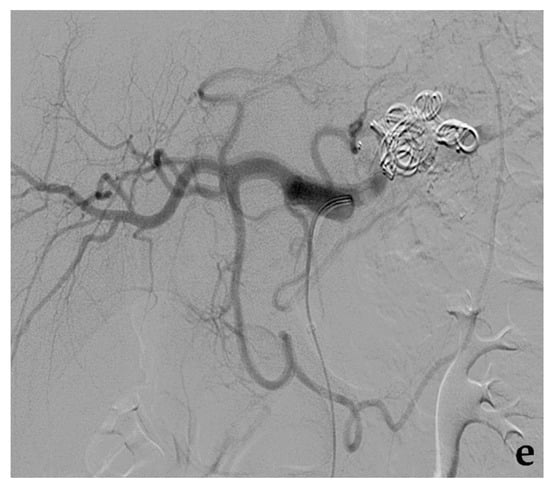

- Venturini, M.; Marra, P.; Augello, L.; Colarieti, A.; Guazzarotti, G.; Palumbo, D.; Lanza, C.; Melissano, G.; Chiesa, R.; De Cobelli, F. Elective embolization of splenic artery aneurysms with an ethylene vinyl alcohol copolymer agent (Squid) and detachable coils. J. Vasc. Interv. Radiol. 2020, 31, 1110–1117. [Google Scholar] [CrossRef] [PubMed]